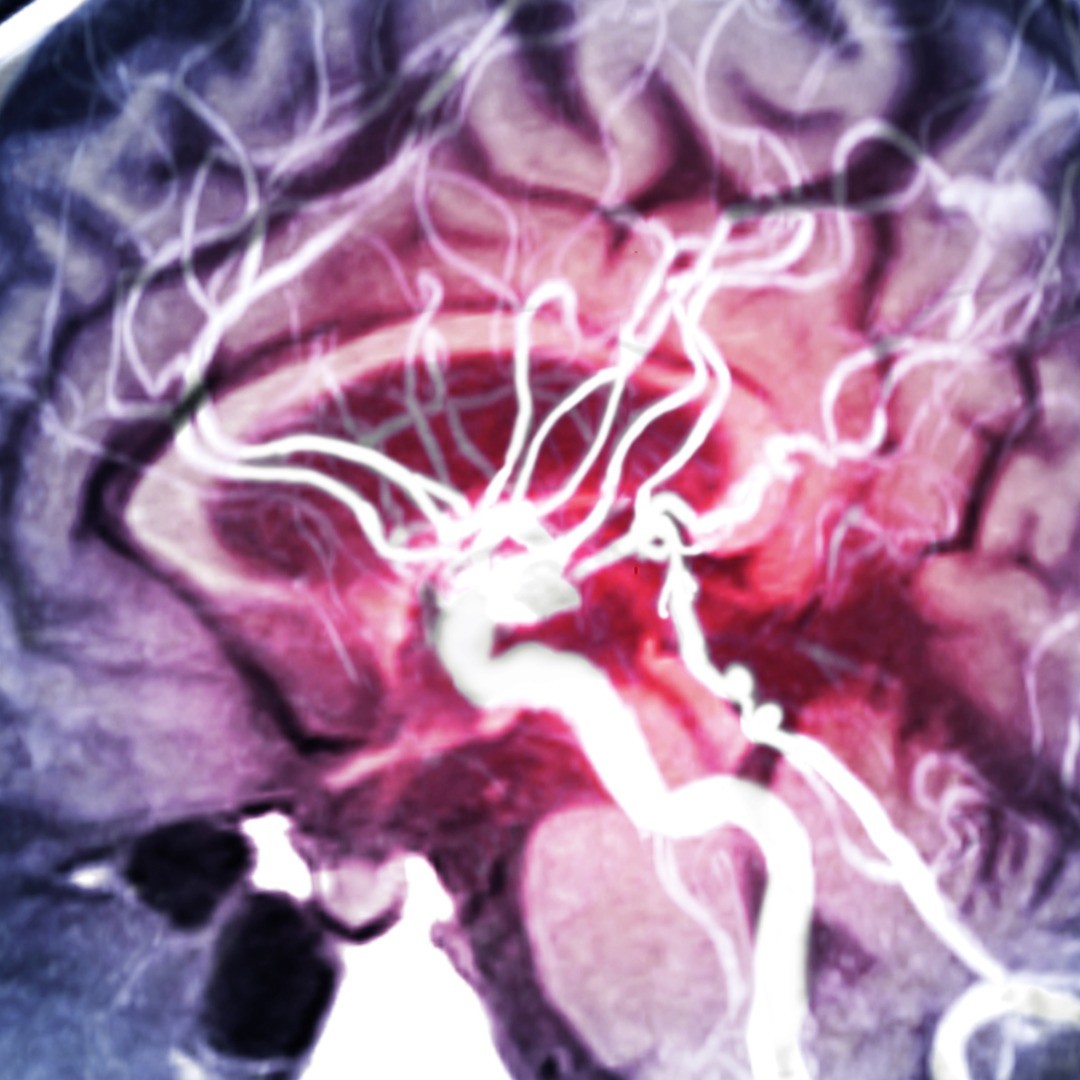

Using a linear accelerator to generate radiation beams, the CyberKnife system under experienced physicians’ guidance can treat tumors anywhere in the body.

Stereotactic radiosurgery provides noninvasive treatment for a variety of inoperable or surgically complex central nervous system (CNS) tumors, such as brain and spine tumors including: